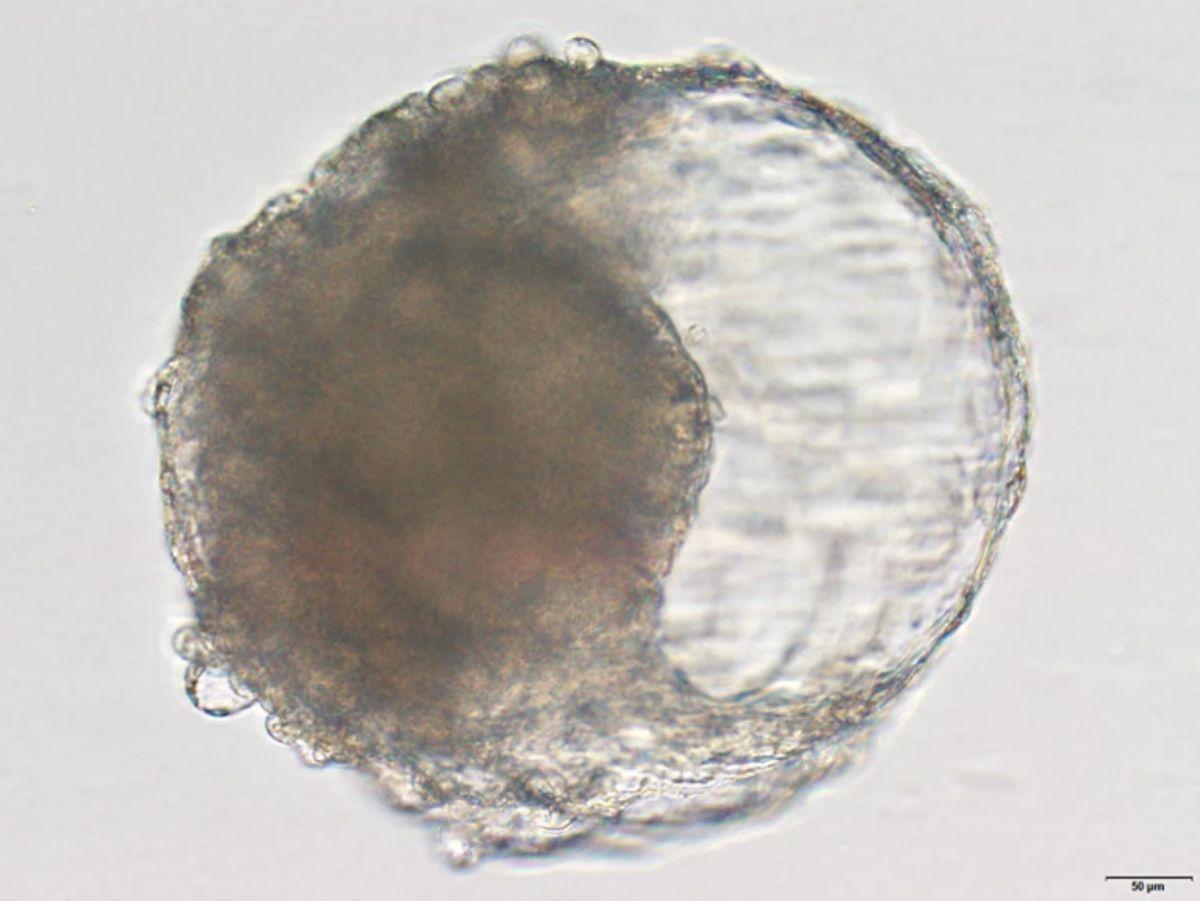

Un blastoide creado a partir de células madre de mono cynomolgus: se asemeja a las primeras etapas de un embrión y desencadenó cambios similares a los de un embarazo cuando se implantó en el útero de un mono hembra. / Crédito: Jie Li.

Un blastoide es una bola de células que se asemeja a las primeras etapas de un embrión, creada en laboratorio mediante células madre. Al ser implantado en el útero de un mono hembra, desencadenó cambios similares a los de un embarazo: el avance podría permitir a los científicos comprender mejor el desarrollo del embrión humano, sin los dilemas éticos de usar células embrionarias reales.

Se sabe que los mecanismos del desarrollo del embrión humano aún no se han comprendido en profundidad, principalmente debido a las dificultades éticas que insume obtener y experimentar con embriones reales. Sin embargo, los científicos son capaces de generar en el laboratorio los llamados blastoides, bolas de células que se asemejan a los blastocistos, los grupos de células en división que se forman entre cinco y seis días después de la fertilización.

En el cultivo celular, los científicos expusieron células madre embrionarias de mono a varios factores de crecimiento, para que se diferenciaran en los tipos de células que se encuentran en los blastocistos naturales. Después de siete días, las células madre habían formado la estructura esférica característica de un blastocisto y se habían diferenciado en los tres linajes celulares que sientan las bases para la formación de tejidos y órganos, en un avance sin precedentes en estudios similares.

A pesar de encontrar características genéticas similares a las observadas en los blastocistos, los científicos apreciaron que los blastoides no eran un reflejo perfecto de las estructuras naturales: algunas células no se pudieron clasificar y otras no expresaron las cantidades necesarias de proteínas. Sobre el día 15, algunos blastoides habían desarrollado características que se asemejaban a una estructura que marca el comienzo de la reorganización de las células para formar el diseño del cuerpo, incluida su configuración habitual.